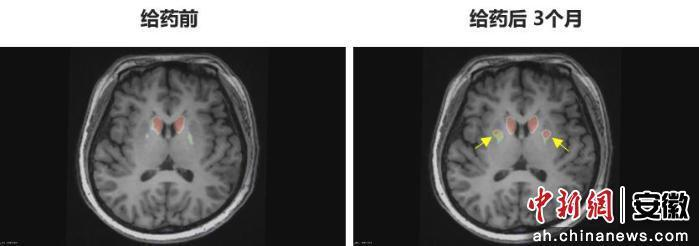

“身體不僵硬了,像正常人一樣?!崩钆啃χf。多年的抖動與“關期”徹底消失,她重新感受到身體的輕盈和心靈的自由。術后影像顯示,移植細胞已在腦內成功定植并發揮功能,醫生稱這些“亮點”是新生多巴胺能神經元的直接證據。

圖為李女士 PET-DAT/MRI融合圖像術前與術后三個月對比。

圖為李女士?PET-DAT/MRI融合圖像術前與術后三個月對比。